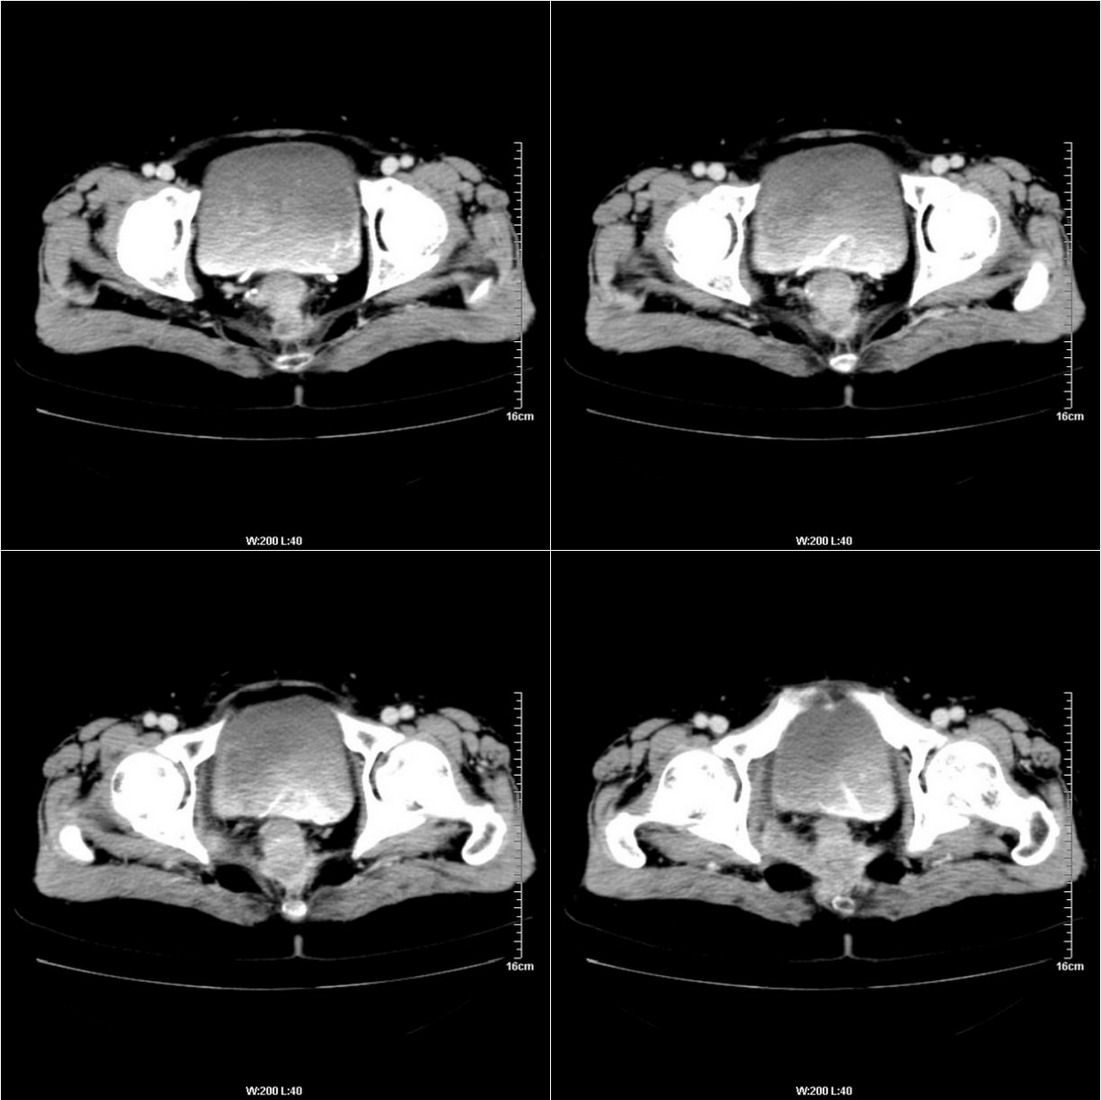

不知道病人的直肠癌手术方式如何,直肠已经全部切除,乙状结肠造瘘于左下腹,肛门应该也没有保留吧?如此,应该是复发了:

病变于肛尾韧带、右侧坐骨肛门窝内并顺右侧肛提肌向右侧闭孔内肌蔓延,骶前软组织内也形成了肿块,麻烦啊!

这个病例还出现了一个有意思的事情:膀胱内在增强的不同时期均有不同形状、位置的高密度出现,并不局限于输尿管开口附近。

是因为尿液中造影剂随输尿管的收缩而排入膀胱内,产生的团片状高密度并进一步弥散而形成的假象吗?渴望哪位老师予以关注并解答,先在此表示感谢了!

膀胱壁见索条状软组织密度影伴强化,可考虑炎性肉芽肿样增生改变,常见于放疗后或慢性感染;直肠及周围软组织见肿块,轻度强化,考虑直肠癌术后复发,并侵犯周围组织